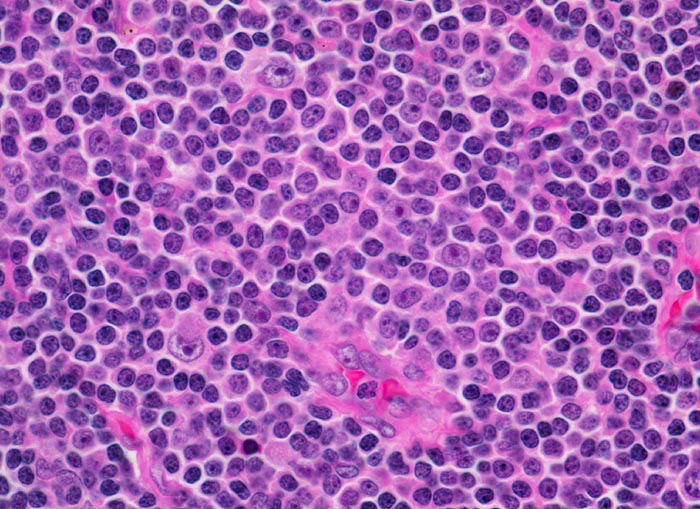

chronische lymphozytische Leukämie vom B-Zell Typ

Lymphknoten, inguinal

Ausschnitt aus einem Proliferationszentrum (Pseudofollikel) mit drei Zellpopulationen:

Kleine Lymphozyten mit wenig Zytoplasma und verklumptem dichtem Chromatin.

Etwas grössere Prolymphozyten mit feiner verteiltem Chromatin und kleinen Nukleolen.

Grosse Paraimmunoblasten mit runden bis ovalen Kernen, fein verteiltem Chromatin und einem zentralen Nukleolus.

Asymptomatische Patientin mit generalisierter Lymphknotenvergrösserung. Zufallsbefund.

630